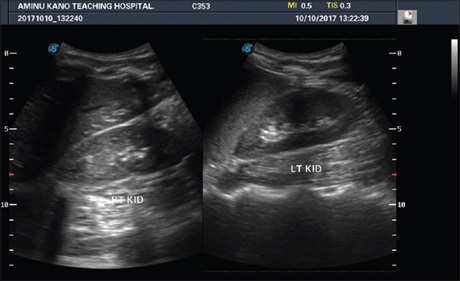

Further observations on the “spaghetti sign” in upper urinary tract hemorrhage

Prof. Funsho Komolafe, Sabir Hussain, Syed Waqar Hussain (Author)

136-140